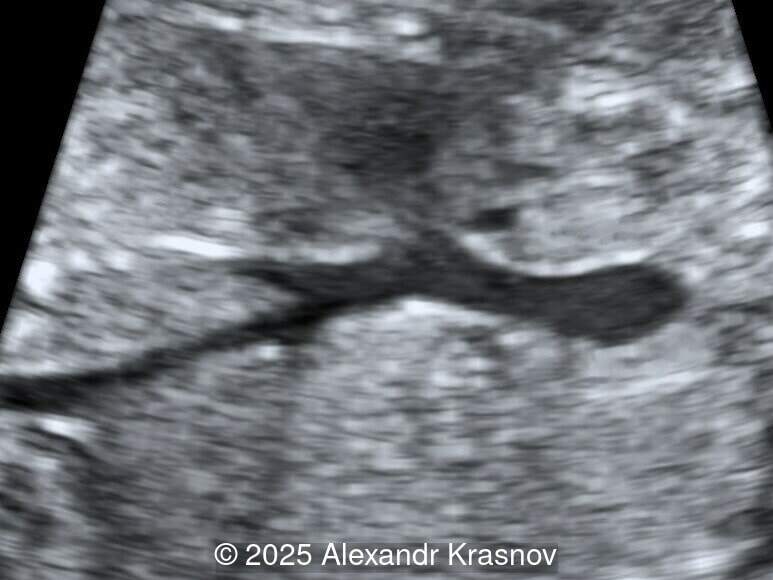

Our ultrasound showed biometry data corresponding to 21 weeks of gestation. During echocardiography, an abnormal drainage of the pulmonary veins was detected in which the pulmonary veins drain into a venous collector linked to the superior vena cava. The four-chamber view and the three-vessel view were altered and raised suspicion of a pathology. The grayscale and color Doppler images of the four-chamber view indicate a smooth posterior wall of the left atrium, increased distance between the left atrium and the descending aorta and the absence of pulmonary veins entering the left atrium (Image 1, 2; Video 1, 2). In the three-vessel view, the diameter of the superior vena cava appears larger than that of the aorta (Image 3, Video 3). In the images of the venae cava, a significant difference is seen between the diameters of the inferior and superior vena cava with significant enlargement of the superior vena cava (Image 4, Video 4). Additionally, there is a pulmonary venous confluent chamber (“twig sign”) behind the left atrium (Image and Video 5). A vertical ascending vein connects the confluent chamber with the superior vena cava where it drains blood from the pulmonary veins (Images 6, 7; Video 6).

Direct markers are based on anatomical features in TAPVR, and their presence usually confirms the diagnosis. Some appear in all types of TAPVR, and others are specific to particular types. A lack of connection between the pulmonary veins and the left atrium or the presence of a confluent chamber can be found in all types of TAPVR. Whereas the presence of an ascending or descending vertical vein is found in supracardiac or infracardiac types. Normal entry of a left and right pulmonary vein at the posterior wall of the left atrium (horn‑like insertion) is absent, which leads to a completely smooth posterior wall in the four-chamber view [6,7]. The “twig sign” represents the entry of the pulmonary veins into a confluent chamber behind the left atrium [7], and is visible in the four‑chamber view except in the cardiac type. In the cardiac type, the confluent vein is located more inferiorly, below the plane of the four‑chamber view and does not form a twig sign, making it more difficult to detect [5]. In supracardiac TAPVR, an ascending vertical vein can be observed in the 3-vessel tracheal view as an additional vessel, usually located at the left of the main pulmonary artery. In infracardiac TAPVR, the descending vertical vein can be seen as an additional vein in the axial abdominal plane [8].

In many cases, direct signs are not visualized, thus identification of indirect signs allow us to suspect this pathology, not diagnose it. They are based on morphological findings such as increased post‑left atrium space, or on hemodynamic changes such as ventricular disproportion, dilated superior vena cava or coronary sinus, and abnormal Doppler waveforms. The presence of a pulmonary venous confluence leads to an increased distance between the left atrium (LA) and the descending aorta (DAo) [9]. While visualization of the confluent chamber may be difficult, objectively measuring the increase in the space behind the left atrium in an axial section may be easier to verify. Various indices have been proposed for this purpose, the most widely used being the “post‑LA space index” described by Kawazu et al [10]. It is calculated as the ratio of the LA‑DAo distance to the diameter of the DAo, proposing a value ≥1.27 as a potential marker of TAPVR. In clinical practice, a cut-off of 1.0 may be more useful to increase detection rates, although this would be at the expense of more false positives. An alternative marker with a similar diagnostic performance and independent of the gestational age is the “left atrial posterior space to diagonal ratio,” which is calculated by dividing the LA‑DAo distance by the left atrial diameter, with an optimal cut-off ≥0.35 [11]. Asymmetric ventricular chamber dimensions with right heart dominance result from extra‑abnormal flow from the pulmonary veins to the right heart, providing a diagnostic clue for TAPVR [9], but this finding is late and not very specific. In supracardiac TAPVR, anomalous pulmonary venous drainage increases blood flow to the collector, which travels to the right atrium through the dilated innominate vein and superior vena cava, visible in the three-vessel trachea and bicaval views [7,12]. In the subcostal view of pediatric echocardiography, the cardiac type is characterized by the “whale’s tail sign,” where left and right pulmonary veins drain into the dilated coronary sinus. Although it is a technically difficult plane to obtain in fetal echocardiography, it has been described by Karmegaraj in a 25-week-old fetus [13]. Spectral Doppler waveforms are typically normal or biphasic in cardiac type, whereas in supracardiac and infracardiac types, the waveforms can be biphasic, monophasic, or continuous [6,7]. Color and spectral Doppler assessment allows the identification of the fetuses with pulmonary venous pathway obstruction and, therefore, at risk for acute postnatal deterioration with severe respiratory distress and cyanosis [14].